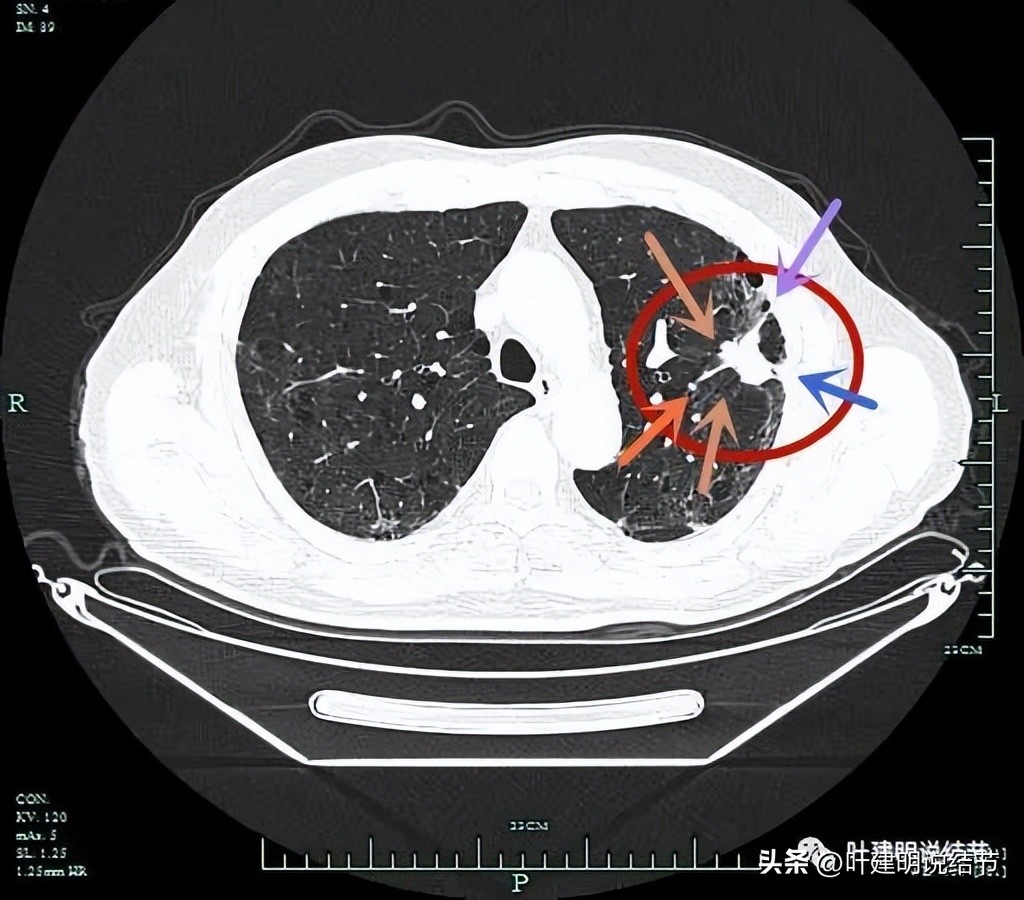

病灶实性,边上条索状并有局灶肺气肿的样子(纹理稀疏)。

病灶实性,有一定膨胀性,表面不平滑。

分叶征(砖色箭头);毛刺征(紫色箭头);胸膜牵拉(蓝色箭头);病灶有膨胀感(红色箭头)。

上图层面明显明显的收缩力、分叶、胸膜牵拉以及血管进入(桔色箭头)。

病灶实性,有纠集感;有胸膜牵拉;有毛刺征;有血管征。